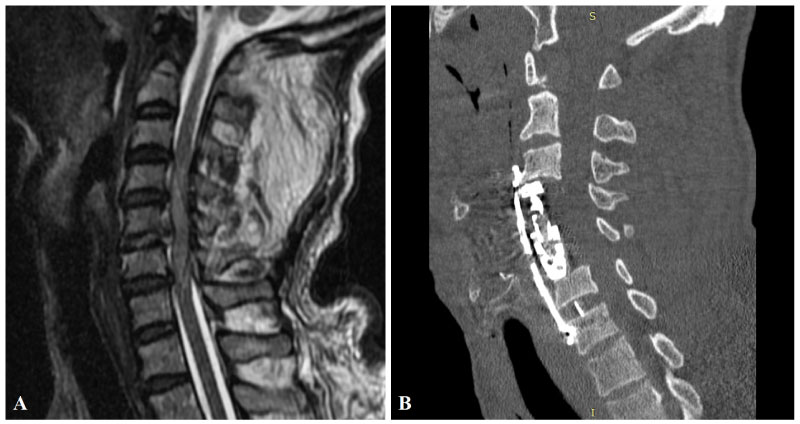

A 44-year-old male patient was admitted to the emergency department for spinal cord injury after a motor vehicle accident. His neurological examination revealed tetraplegia. Spinal radiological imaging revealed diffuse spinal cord edema (Figure 3A) and 2 mm epidural collection at C3-7 levels. Hemodynamic stabilization of the patient who has a spinal shock state was provided in the neuro-intensive care unit. C4-5 corpectomy and C6-7 discectomy were performed urgently to provide spinal decompression. The fusion was achieved using a distractible cage and a PEEK cage (Figure 3B). Anterior plate stabilization was performed (Figure 4A and Figure 4B). The patient's follow-up and treatment continued in the neuro-intensive care unit with the support of mechanical ventilation. Two months after the operation, a screw was detected in the right lung distal bronchus in the routine PA chest X-ray (Figure 4E). Spinal imaging revealed that the upper left screw which was fixed to the C3 corpus was not in place (Figure 4C and Figure 4D) and that it had migrated to the thoracic cavity after creating a perforation in the pharyngeal wall. The patient underwent rigid bronchoscopy, and the screw was removed. Upper fixation screws were revised and stabilized surgically. Since the patient had a tracheostomy and receives the enteral tube feeding, the pharyngeal perforation was left to secondary wound healing. The patient was referred to the physical therapy center after three months from the operation.

Figure 3: Preoperative MRI of the patient in the sagittal plane. A) Showing traumatic posterior C5-6 disc herniation, diffuse spinal cord edema and 2 mm epidural fluid collection at C3-7 levels. Postoperative cervical CT; B) Showing C4-5 corpectomies (and fusion with a distractible cage) and C5-6 discectomy (and fusion with a PEEK cage) and stabilization with anterior plate and screws. View Figure 3